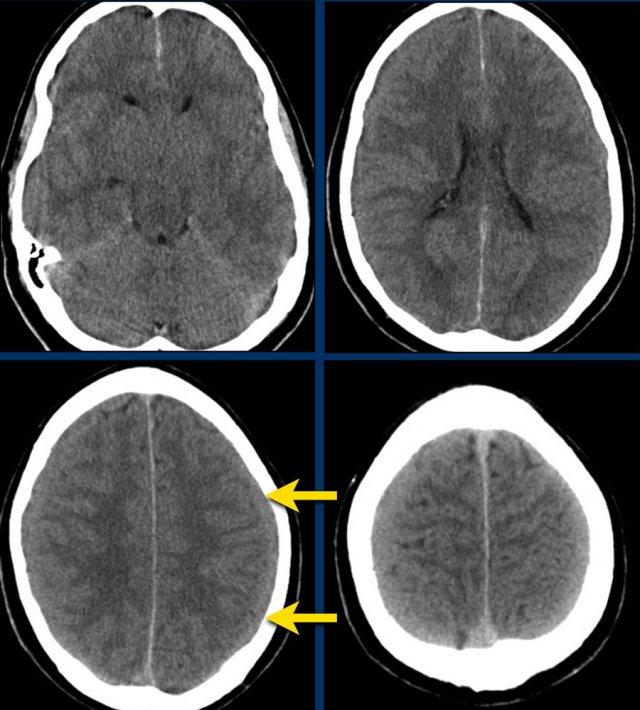

Bệnh nhân này có tụ máu dưới màng cứng cấp tính.

Có sự dịch chuyển đường giữa (hình bên trái).

Bệnh nhân đã được phẫu thuật và khối tụ máu được dẫn lưu (hình bên phải).

Các hình ảnh cho thấy tụ máu dưới màng cứng.

Lưu ý rằng khối tụ máu có cả vùng tăng tỷ trọng và đồng tỷ trọng.

Hình ảnh này có thể gặp trong chảy máu siêu cấp tính, nhưng cũng có thể gặp trong trường hợp chảy máu tái phát.

Có sự dịch chuyển các cấu trúc đường giữa kèm tắc nghẽn lưu thông dịch não tủy, dẫn đến giãn sừng thái dương của não thất bên phải (mũi tên).

Đây là trường hợp tụ máu dưới màng cứng đồng tỷ trọng rất khó phát hiện (các mũi tên).

Lưu ý rằng ở mức cắt cao hơn có tụ máu dưới màng cứng hai bên.